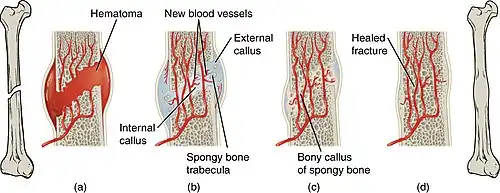

The natural process of healing a fracture starts when the injured bone and surrounding tissues bleed, forming a fracture hematoma. The blood coagulates to form a blood clot situated between the broken fragments.[6] Within a few days, blood vessels grow into the jelly-like matrix of the blood clot. The new blood vessels bring phagocytes to the area, which gradually removes the non-viable material. The blood vessels also bring fibroblasts in the walls of the vessels and these multiply and produce collagen fibres. In this way, the blood clot is replaced by a matrix of collagen. Collagen's rubbery consistency allows bone fragments to move only a small amount unless severe or persistent force is applied.

At this stage, some of the fibroblasts begin to lay down bone matrix in the form of collagen monomers. These monomers spontaneously assemble to form the bone matrix, for which bone crystals (calcium hydroxyapatite) are deposited in amongst, in the form of insoluble crystals. This mineralization of the collagen matrix stiffens it and transforms it into bone. In fact, bone is a mineralized collagen matrix; if the mineral is dissolved out of bone, it becomes rubbery. Healing bone callus on average is sufficiently mineralized to show up on X-ray within 6 weeks in adults and less in children. This initial "woven" bone does not have the strong mechanical properties of mature bone. By a process of remodelling, the woven bone is replaced by mature "lamellar" bone. The whole process may take up to 18 months, but in adults, the strength of the healing bone is usually 80% of normal by 3 months after the injury.